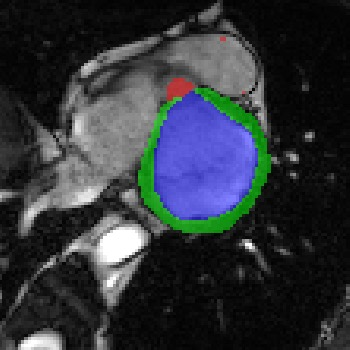

Transformers, the default model of choices in natural language processing, have drawn scant attention from the medical imaging community. Given the ability to exploit long-term dependencies, transformers are promising to help atypical convolutional neural networks (convnets) to overcome its inherent shortcomings of spatial inductive bias. However, most of recently proposed transformer-based segmentation approaches simply treated transformers as assisted modules to help encode global context into convolutional representations without investigating how to optimally combine self-attention (i.e., the core of transformers) with convolution. To address this issue, in this paper, we introduce nnFormer (i.e., Not-aNother transFormer), a powerful segmentation model with an interleaved architecture based on empirical combination of self-attention and convolution. In practice, nnFormer learns volumetric representations from 3D local volumes. Compared to the naive voxel-level self-attention implementation, such volume-based operations help to reduce the computational complexity by approximate 98% and 99.5% on Synapse and ACDC datasets, respectively. In comparison to prior-art network configurations, nnFormer achieves tremendous improvements over previous transformer-based methods on two commonly used datasets Synapse and ACDC. For instance, nnFormer outperforms Swin-UNet by over 7 percents on Synapse. Even when compared to nnUNet, currently the best performing fully-convolutional medical segmentation network, nnFormer still provides slightly better performance on Synapse and ACDC.